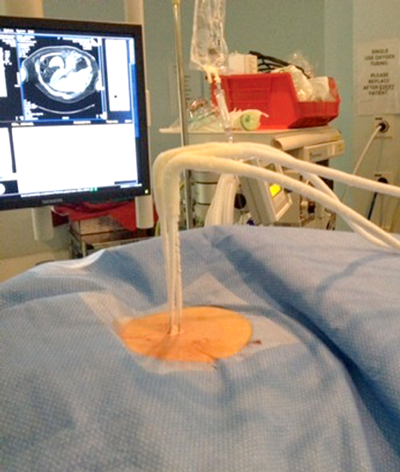

Under imaging guidance a series of cryoprobes are placed into the target lesion with the patient in the prone oblique position. Often this is performed under general anaesthetic with CT guidance, and this is our method of choice. We believe CT offers the most accurate depiction of the tumour and treatment boundaries in all planes, and permits precise probe placement with tolerances of 3-4mm. MRI is also set to evolve as an effective and robust guidance tool in the next few years. The size and morphology of the tumour dictates the number of probes required and their configuration (Figure 2). Broadly speaking, the probes should be placed approximately 1cm from the tumour edge and less than 2cm apart.

Figure 2: Probe placement.

Once the probes are appropriately positioned it may be necessary to protect vulnerable adjacent structures, such as the bowel, pancreas or ureter. The adjunctive techniques most commonly employed to achieve this protection involve the injection of fluid (hydrodissection) or gas (air dissection) to displace at risk structures (Figure 3).

Figure 3: Peri-treatment image depicting cryoprobes within the iceball

and a protective layer of contrast tinted hydrodissection.